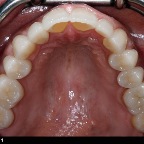

Vollkeramik

vorher

nachher 1

nachher 2

nachher 3

nachher 4

nachher 5